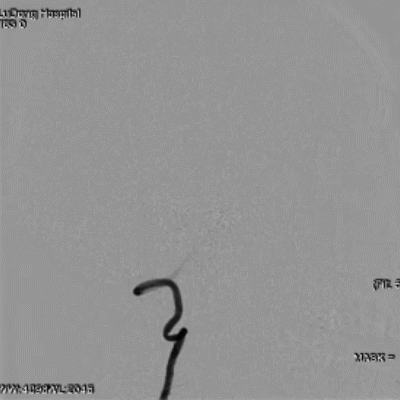

于左侧锁骨下动脉。

导丝怎么扩【载药时代 球扩天下】NOVA DES®颅内药物洗脱支架在症状性颅内动脉狭窄中的应用—烟台鲁东医院使用体会二例!_https://www.jmylbn.com_新闻资讯_第7张

微导丝置于大脑后动脉远端,造影显示左侧V4段重度狭窄,前向血流显著延迟。